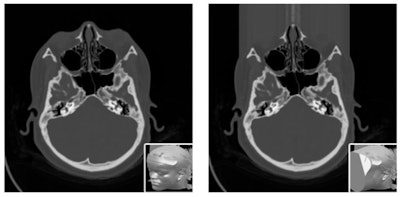

Sensitive features can be automatically detected and hidden by covering the face with a shapeless mask of pseudorandom noise. Image courtesy of N. Roduit, University Hospital of Geneva."We have to tell them, 'We will do everything we can to keep your data anonymized, but there is always a risk.' If someone wants to expend enough time and effort to find you, they will, but our responsibility is to minimize that risk as much as possible," he said.